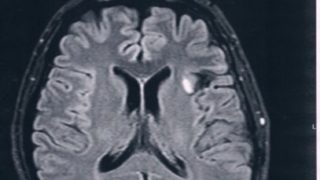

GLIOMA:手術後60ヶ月目の検査

前回、造影剤を使ってMRI検査をして悪性転化がないことが確認されたので、今回は6か月おきの通常の定期検査。特に変化はなく問題なしとのこと。ただし、悪性転化しやすい腫瘍の種類(びまん性星細胞腫グレード2)であるとのことで、1年に一回は造影剤を...